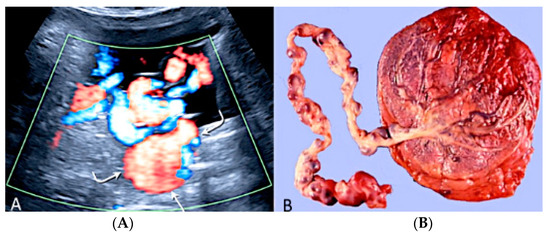

3.2.7. Umbilical Cord Hemangioma